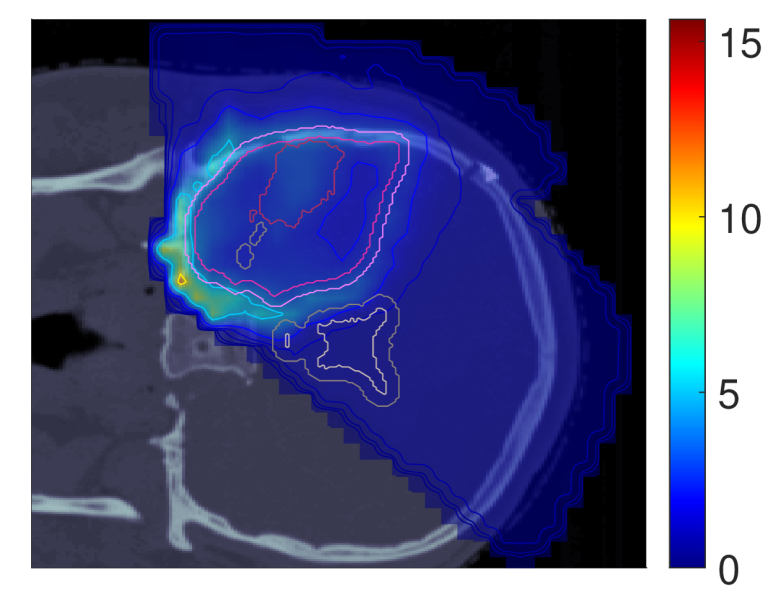

Figure 3 shows the slice images with the optimal dose distributions, where the POLO model-based objective functions are displayed vertically and the NTCP levels horizontally.

NTCP30 %NTCP\approx{$30\text{\,}\mathrm{\char 37\relax}$} NTCP20 %NTCP\approx{$20\text{\,}\mathrm{\char 37\relax}$} NTCP10 %NTCP\approx{$10\text{\,}\mathrm{\char 37\relax}$}

dRBE,fxd_{RBE,fx} (NTCPp)(NTCP_{p})

Refer to caption Refer to caption Refer to caption

dRBE,fxd_{RBE,fx} (LSEp~)(LSE_{\tilde{p}})

dRBE,fxd_{RBE,fx} (H~p)(\tilde{H}_{p})

dRBE,fxd_{RBE,fx} (H~p~)(\tilde{H}_{\tilde{p}})

Figure 3: Optimal slice images of the RBE-weighted fractional dose dRBE,fxd_{RBE,fx} (in Gy\mathrm{Gy}(RBE)) for NTCPpNTCP_{p}, LSEp~LSE_{\tilde{p}}, H~p\tilde{H}_{p} and H~p~\tilde{H}_{\tilde{p}} at different NTCP levels. The objective functions behave similarly in that dose is reduced to achieve a lower NTCP value. However, they differ in the strength of the dose reduction inside and the impact on the dose outside the target volume, particularly in the VS. NTCPpNTCP_{p} and H~p\tilde{H}_{p} show comparable dose results, while LSEp~LSE_{\tilde{p}} and H~p~\tilde{H}_{\tilde{p}} more aggressively eliminate dose in the target volume.

We observe intra-functional similarities of the objectives from a reduction of the dose values with decreasing NTCP level, especially in the overlapping regions to the VS, but also within the target volumes. NTCPpNTCP_{p} manages to reduce the risk estimate by almost 26 %26\text{\,}\mathrm{\char 37\relax} compared to the baseline plan without affecting target coverage (ΔPTVd95RBE,fx0.03\Delta_{\text{PTV}}\text{d95}_{RBE,fx}\approx{0.03}, ΔGTVd95RBE,fx0.001\Delta_{\text{GTV}}\text{d95}_{RBE,fx}\approx{0.001}), which can be attributed to the dose contraction away from the VS. This is even more pronounced when lowering the NTCP level to 10 %10\text{\,}\mathrm{\char 37\relax}, but is then accompanied by a loss in target coverage (ΔPTVd95RBE,fx0.07\Delta_{\text{PTV}}\text{d95}_{RBE,fx}\approx{0.07}, ΔGTVd95RBE,fx0.02\Delta_{\text{GTV}}\text{d95}_{RBE,fx}\approx{0.02}).

From an inter-functional perspective H~p\tilde{H}_{p} seems to behave very similarly, with only minor deviations in the dose slice. In contrast, we find that LSEp~LSE_{\tilde{p}} and H~p~\tilde{H}_{\tilde{p}} modulate the dose more strongly, with local inhomogeneities already at an NTCP level of 30 %30\text{\,}\mathrm{\char 37\relax}. Here, LSEp~LSE_{\tilde{p}} only marginally reduces the dose in the upper part of the VS but restricts the dose exposure in the target volume (ΔPTVd95RBE,fx0.26\Delta_{\text{PTV}}\text{d95}_{RBE,fx}\approx{0.26}, ΔGTVd95RBE,fx0.1\Delta_{\text{GTV}}\text{d95}_{RBE,fx}\approx{0.1}). Even more, target coverage breaks down at an NTCP level of 10 %10\text{\,}\mathrm{\char 37\relax} (ΔPTVd95RBE,fx0.51\Delta_{\text{PTV}}\text{d95}_{RBE,fx}\approx{0.51}, ΔGTVd95RBE,fx0.24\Delta_{\text{GTV}}\text{d95}_{RBE,fx}\approx{0.24}). One reason could be the focus of LSEp~LSE_{\tilde{p}} on maximum points, causing a “notch” in the high dose region around the overlap of CTV/PTV and VS at an NTCP level of 20 %20\text{\,}\mathrm{\char 37\relax}.

H~p~\tilde{H}_{\tilde{p}}, on the other hand, results in an immediate dose contraction, with higher concentration on the GTV with lower NTCP level. Similar to LSEp~LSE_{\tilde{p}}, target coverage is drastically affected at 10 %10\text{\,}\mathrm{\char 37\relax} NTCP (ΔPTVd95RBE,fx0.71\Delta_{\text{PTV}}\text{d95}_{RBE,fx}\approx{0.71}, ΔGTVd95RBE,fx0.22\Delta_{\text{GTV}}\text{d95}_{RBE,fx}\approx{0.22}), which may be due to the increased scale of the function values and gradients of the linearly reformulated POLO model and therefore the higher impact of LSEp~LSE_{\tilde{p}} and H~p~\tilde{H}_{\tilde{p}} on the plan.